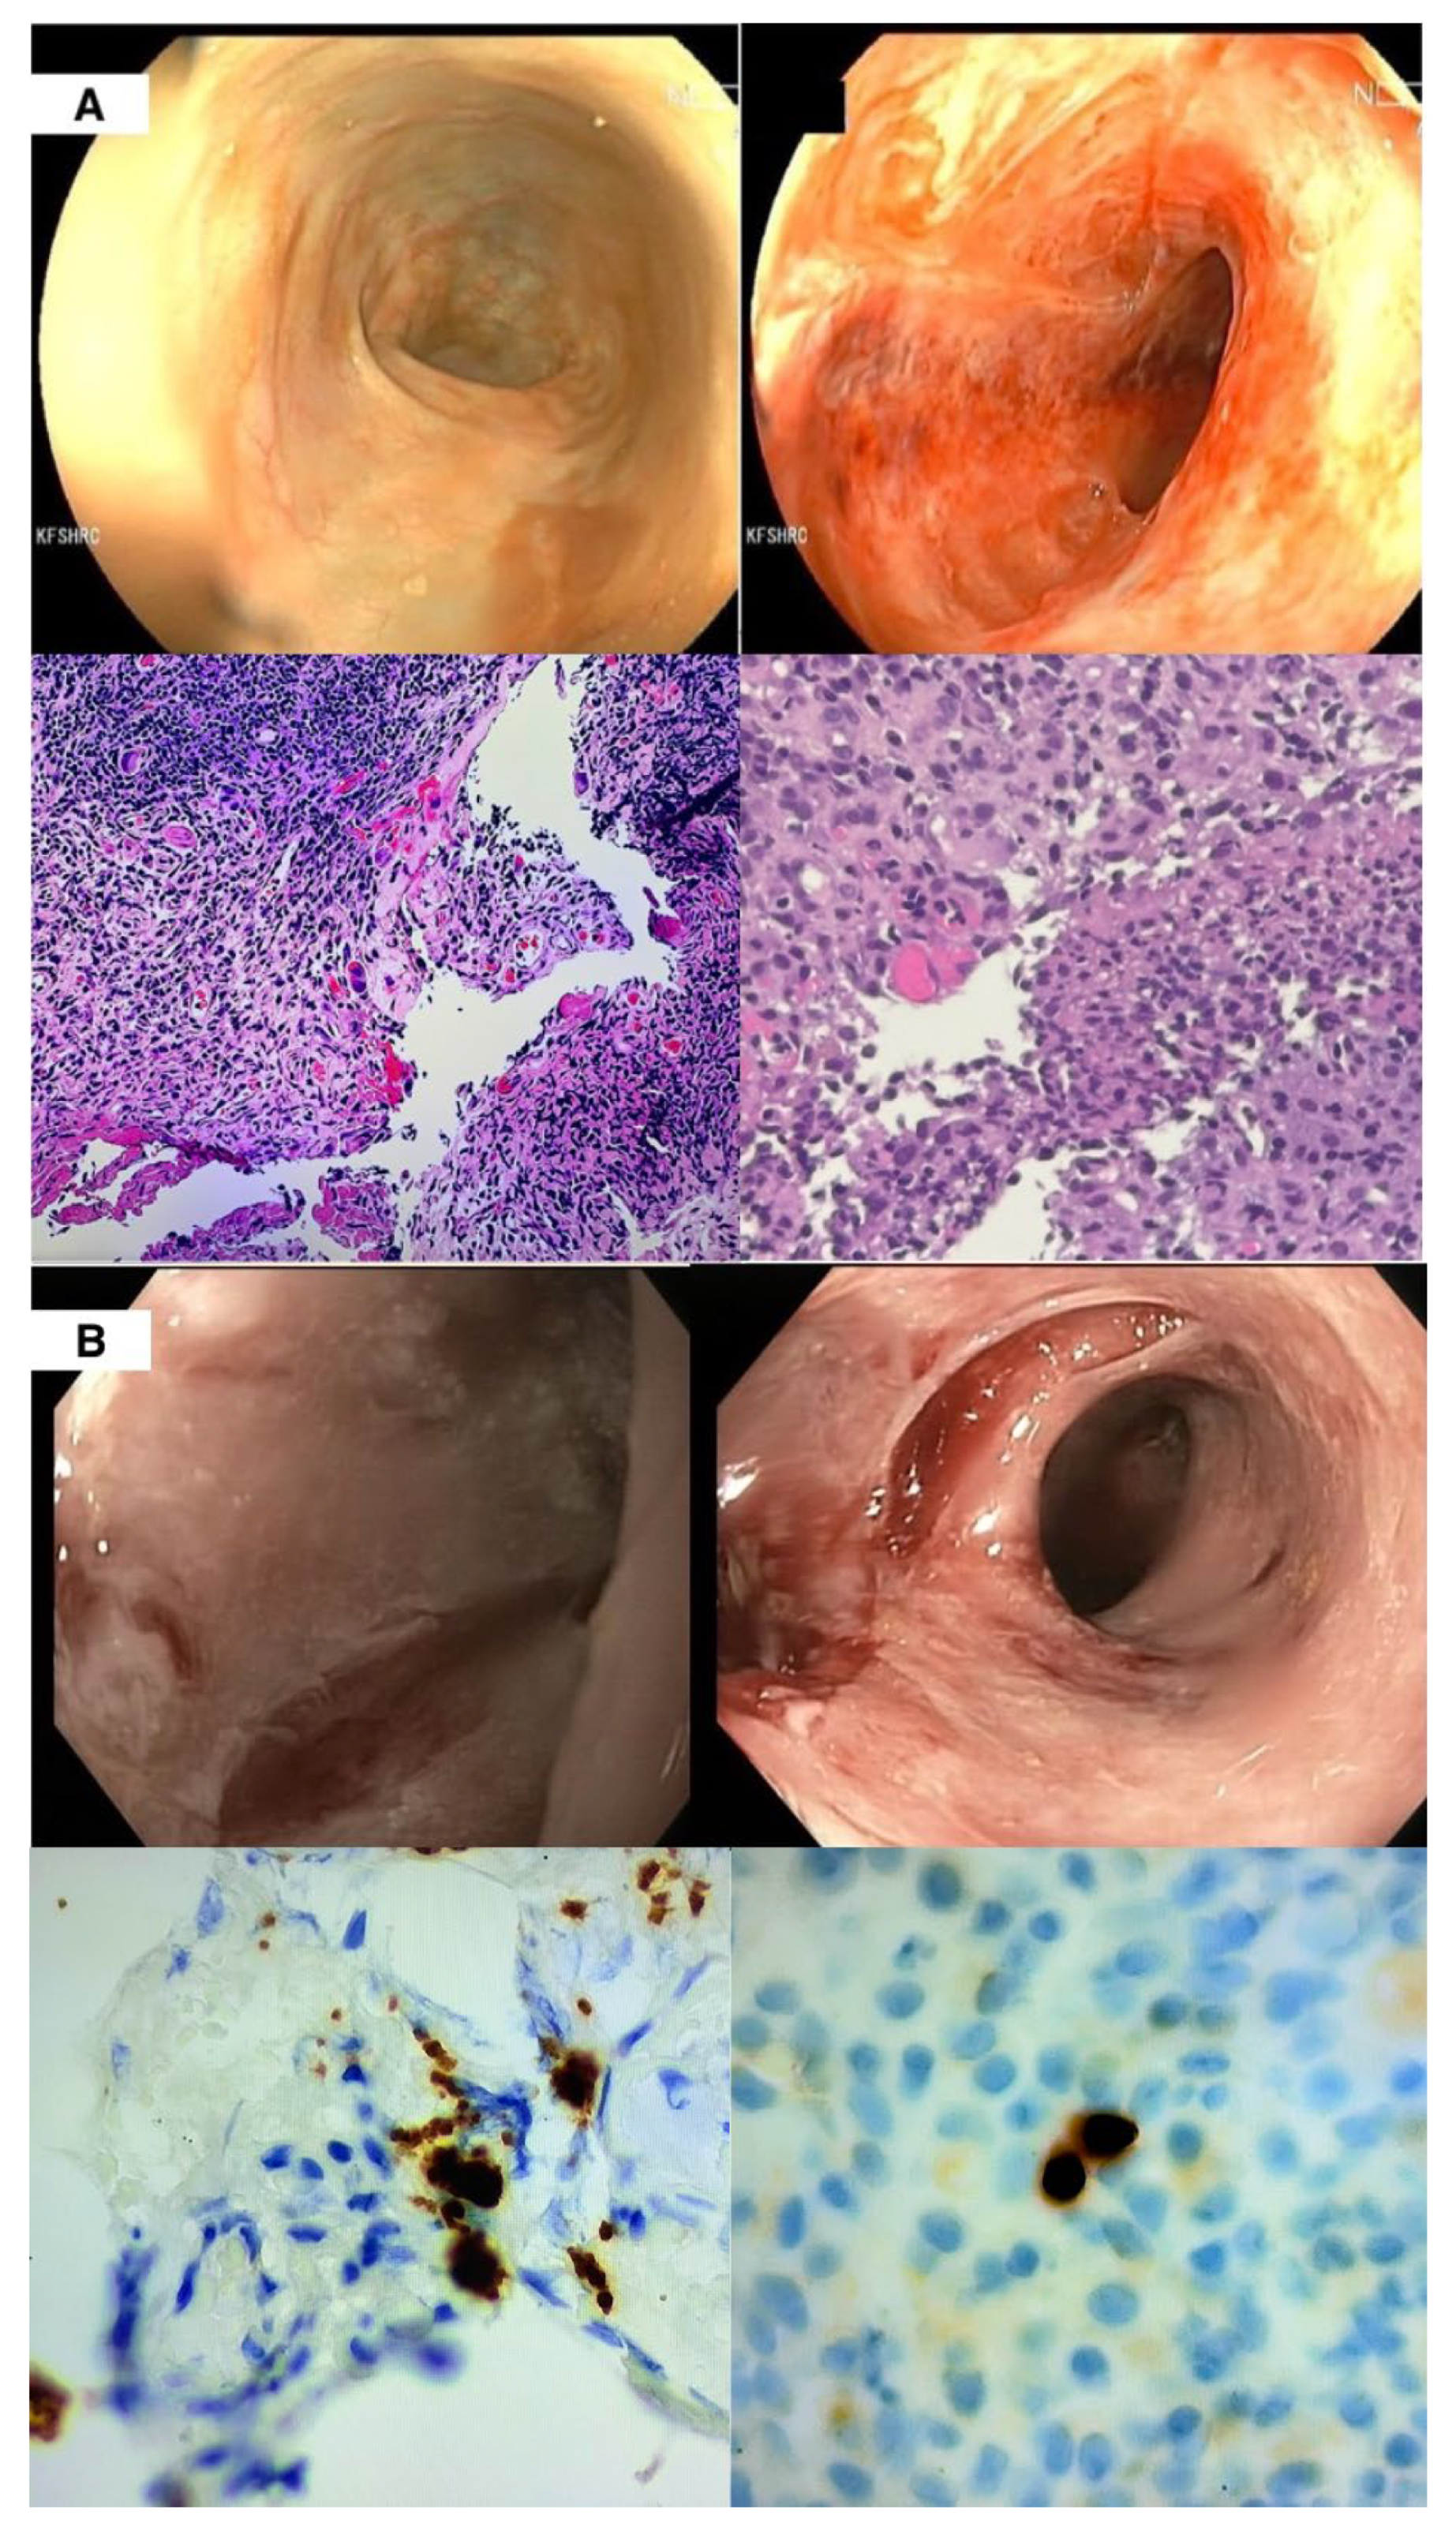

2. Clinical Case